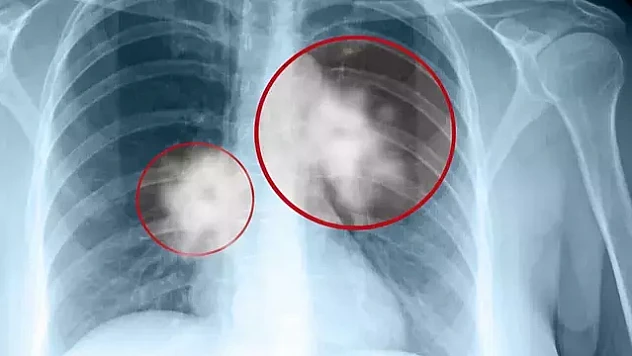

bilgisayarlı tomografi